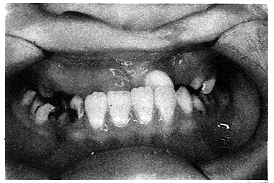

患者女,8岁,替牙期,左侧完全性唇腭裂术后伴牙槽突裂。

检查:39.gif (84 bytes)近中,40.gif (84 bytes)中性,反覆 合Ⅱ°,反覆盖Ⅱ°,前牙及右侧后牙全部反合,下颌可后退,X线片示左上侧切牙先天缺失。

诊断:安氏ⅢS,毛氏Ⅱ1+Ⅲ2+Ⅳ1。

矫治:

(1)上颌垫活动矫治器:3个月。

(2)上颌固定矫治器+下颌活动矫治器:9个月,术前正畸共12个月。

(3)牙槽突植骨术:9岁,取髂骨髓质骨。

(4)术后2年恒尖牙从植骨区萌出。

(5)恒牙期正畸治疗:上下固定矫治器。

(6)义齿修复侧切牙(图2~4)。